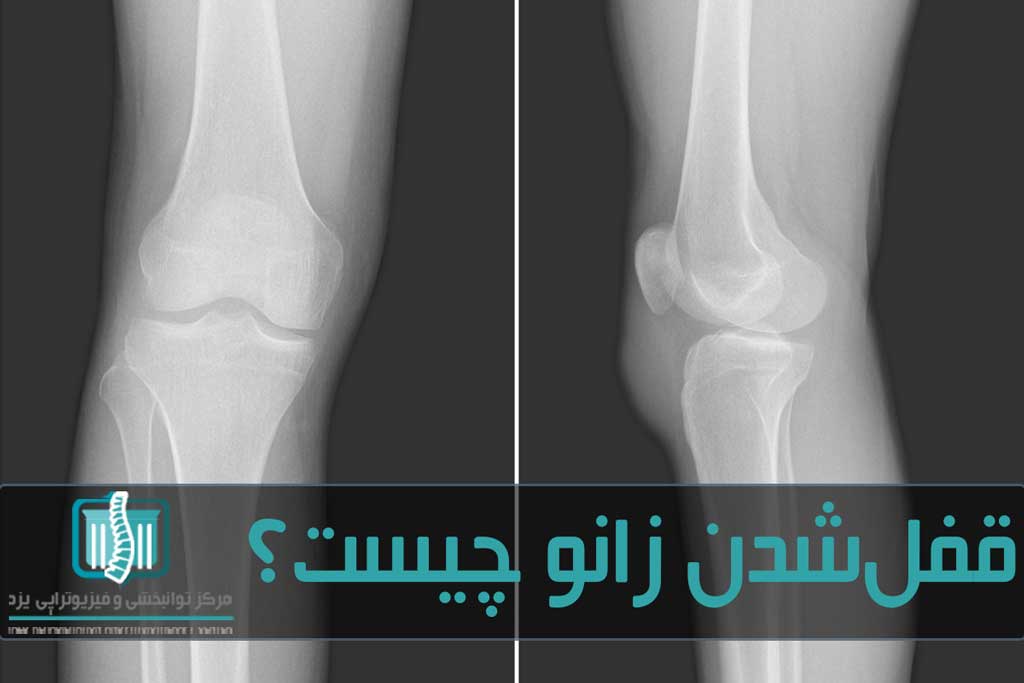

برای آنکه بدانید قفل شدن زانو چیست، لازم است ابتدا نگاهی به ساختار مفصل زانو بیندازید. مفصلی پیچیده که دو استخوان مهم ران و ساق پا را بهم متصل میکند. در این مفصل استخوانهای کشکک زانو قرار دارند که یک تکه استخوان کوچک هم در کنار آن است. دو استخوان ران و ساق پا توسط رباطها به یکدیگر وصل شدهاند. همچنین استخوانها توسط تاندونها به عضلات ران و ساق پا میرسند. در داخل مفصل، دو تکه غضروفیc شکل قرار دارد که مانند بالشتکی بین دو استخوان ران و ساق عمل میکند، این دو تکه مینیسک زانو نام دارند. مینیسک ضربهها و شوکهای وارده به زانو را جذب کرده و به حرکت روانتر مفصل کمک میکند. علاوه بر اینها استخوان کشکک زانو اجزای مفصل زانو را در برگرفته است.

مجموعه این اجزا با هم مفصل زانو را تشکیل دادهاند، این ساختار بهگونهای است که باعث میشود زانو بتواند به سمت جلو و عقب خم و راست شود. تا حدودی بچرخد و همچنین توان تحمل وزن بدن را داشته باشد. حالت قفل شدن زانو حالتی است که در آن زانو وقتی خم یا راست است، امکان تغییر موقعیت خود را از دست میدهد. یعنی اگر پا در حالت صاف قفل شود، نمیتواند خم شود. یا اگر خم شده باشد، توان صاف شدن ندارد.